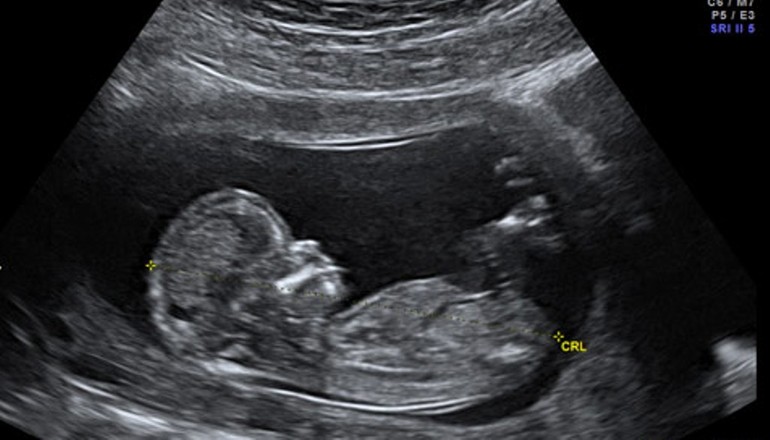

Thời điểm được cho là bắt đầu sự sống, chính xác là hình thành bào thai (con người) hiện trên thế giới có nhiều quan điểm khác nhau. Theo Phật giáo, có ba nhân tố căn bản hòa hợp để hình thành nên bào thai. Đó là do tinh cha, huyết mẹ cùng thần thức hòa hợp mà thành.

Như vậy có thể xác định, thời khắc tinh trùng xâm nhập vào trứng (cả tự nhiên cùng các phương pháp thụ tinh nhân tạo, thụ tinh trong ống nghiệm) đồng thời thần thức (hương ấm) phải có mặt để cùng hội nhập, chính là lúc đầy đủ nhân duyên để hình thành bào thai.

Đây là quan điểm chính thống của Phật giáo về thời điểm hình thành con người. Từ cơ sở này, Phật giáo thiết lập các giá trị đạo đức, cách thức ứng xử đối với thai nhi (tuy còn trứng nước) như một con người thực thụ.